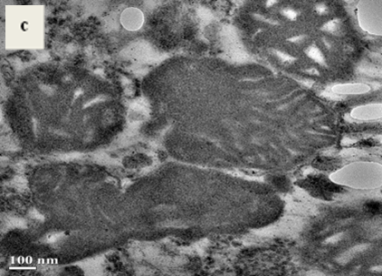

Fig. 4: Microphotographs of the liver mitochondria from normal control mice and N-nitroso dibutyl amine (DBN) treated mice at different magnification 2000x, 12000x, 15000x. (a) Mitochondrial population from treated mice at 2000x. (b) Mitochondrial population from normal mice 2000x. (c) Defragmented and denser cristae in treated mice at 12000x. (d) Normal mitochondria at 12000x. (e) Diffused membrane, larger vacuoles and deformed mitochondria in treated mice at 15000x. (f) Normal mitochondria at 15000x

On comparing the micrographs obtained from TEM at various magnifications 2000x, 10000x, 15000x (fig. 4) significant changes were observed. Electron microscopy pictures revealed that mitochondria were barely identifiable in the case of DBN treated mice. It was found that most of the mitochondria from DBN treated mice had distorted and looked like remnants (fig. 4b). Mitochondria showed variability in number (fig. 4a and 4b), size and shape (fig. 4c and 4d). The cristae membranes had greatly reduced and disorganized in the case of the treated mice whereas in normal mice they looked normal and organized. Cristae appeared denser and mitochondrial fragmentation was seen in treated mice.

The inner and outer membrane of the mitochondria was found to be disrupted, and most of the mitochondria were condensed. They were found to have larger vacuoles whereas the mitochondria in control mice showed no such changes. They had well-defined membrane along with normal vacuoles.

The main target of the present investigation was to see whether DBN effects the liver mitochondria and its surface membrane protein or not. Transmission electron microscopy allows seeing the mitochondrial morphology and their overall organization. So to see the morphological changes TEM was done. Intact mitochondria isolated from the liver of both treated and control mice were observed microscopically. A drastic distortion in shape and size and abnormalities in the population of mitochondria was observed in the present study (fig. 4). Mitochondria from the treated mice appeared to bigger in size than from the normal. It was reported in the studies that mitochondria are barely identifiable in hepatocellular carcinoma, and looked like mitochondrial ghosts [38]. The cellular function of mitochondria is reflected in their structure [39]. Defects in mitochondrial function have been suspected to play an important role in the development and progression of cancer [40, 41]. Highly disrupted membrane and large vacuoles were seen in treated mice. Enlarged, denser and distorted cristae compartments were also found in DBN treated mice which were seen in regular and normal condition in normal mice. The mitochondrial swelling with distortion of the cristae was found to be associated with hypoxic–ischemic conditions [42]. It’s been reported that mitochondrial swelling with partial or total cristolysis suggests that the ability of neoplastic cells to generate ATP by mitochondrial oxidative phosphorylation would be diminished [43]. Studies have shown that mitochondrial morphology is crucially linked to energy metabolism resulting enhanced respiration which correlates with an enlarged cristae compartments and interconnected network [44]. Mitochondria from the treated mice seemed to be diffused and fragmented. It has been showed in studies that mitochondria from the liver tumors were more fragile than from the normal liver mitochondria [45]. Mitochondrial fragmentation is the result of excessive fission, and small punctuate mitochondria can be derived from mitochondrial fission [46]. Fragmentation of the mitochondrial network appears to occur in those situations where the mitochondrial inner membrane potential was abnormal [47] and was in response to oxidative phosphorylation impairment [48]. The fragmentation of mitochondria does not found to evoke apoptosis [46].